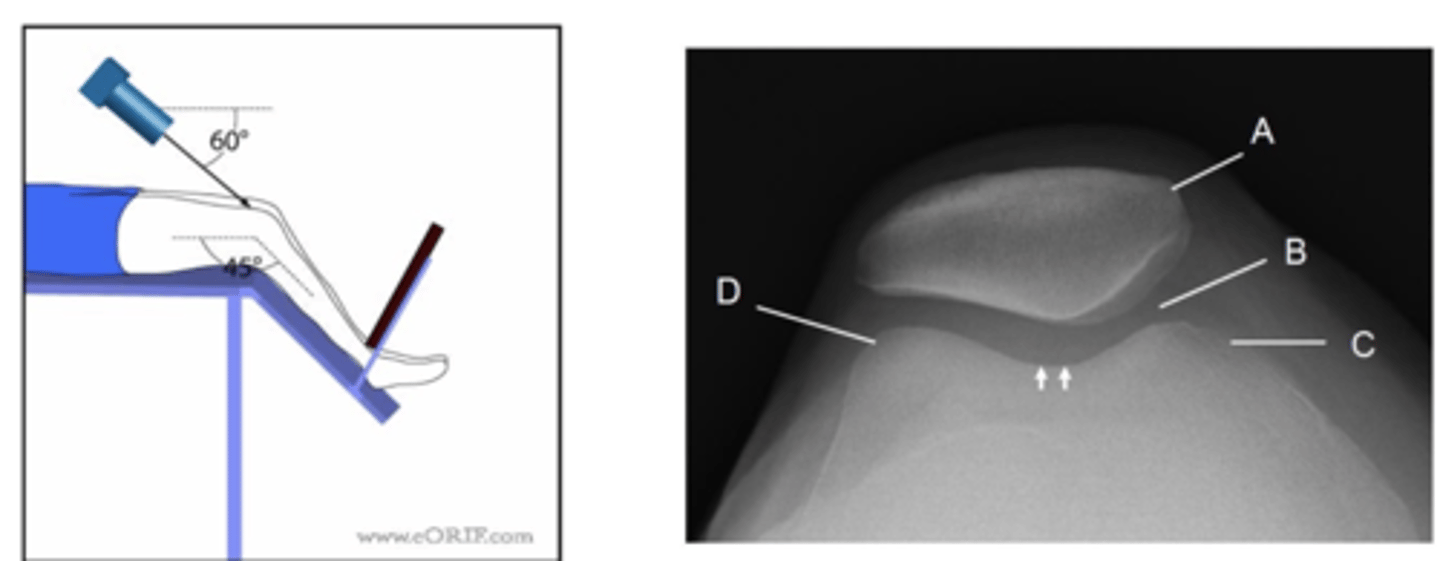

Describe, in the detail, how you would position the PATIENT for a SKYLINE projection of the knee (supero-inferior)

1. The patient sits on the x-ray couch with affected knee flexed over the edge.

2. If possible the knee should be flexed to 45 degrees.

3. Patient to lean back whilst keeping affected knee still to avoid primary beam.

4. The IR should be at the level of the inferior border of the tibial tuberosity

How should you position the X-RAY TUBE for a infero-superior prone SKYLINE KNEE projection?

SID

Central ray

Centring point

SID: 115cm

Central ray: angled 15 degrees towards the knee (avoiding the toes)

Centring point: behind the patella